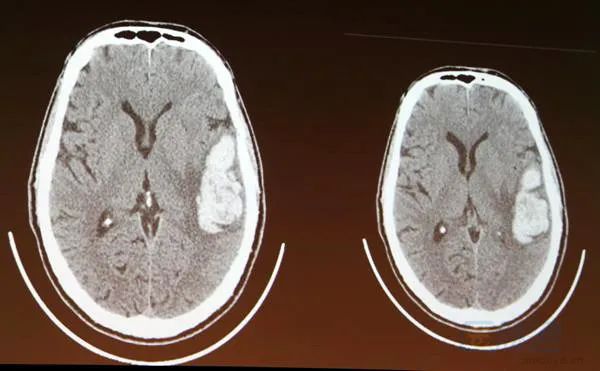

脑出血的CT表现

头颅CT平扫是简单快速的检查,可明确HICH诊断。有时根据情况还需CTA、MRI、MRA、MRV及DSA排除。平扫CT和CTA上的“斑点征”“黑洞征”“混杂征”及“岛征”有助于判断血肿扩大的风险。